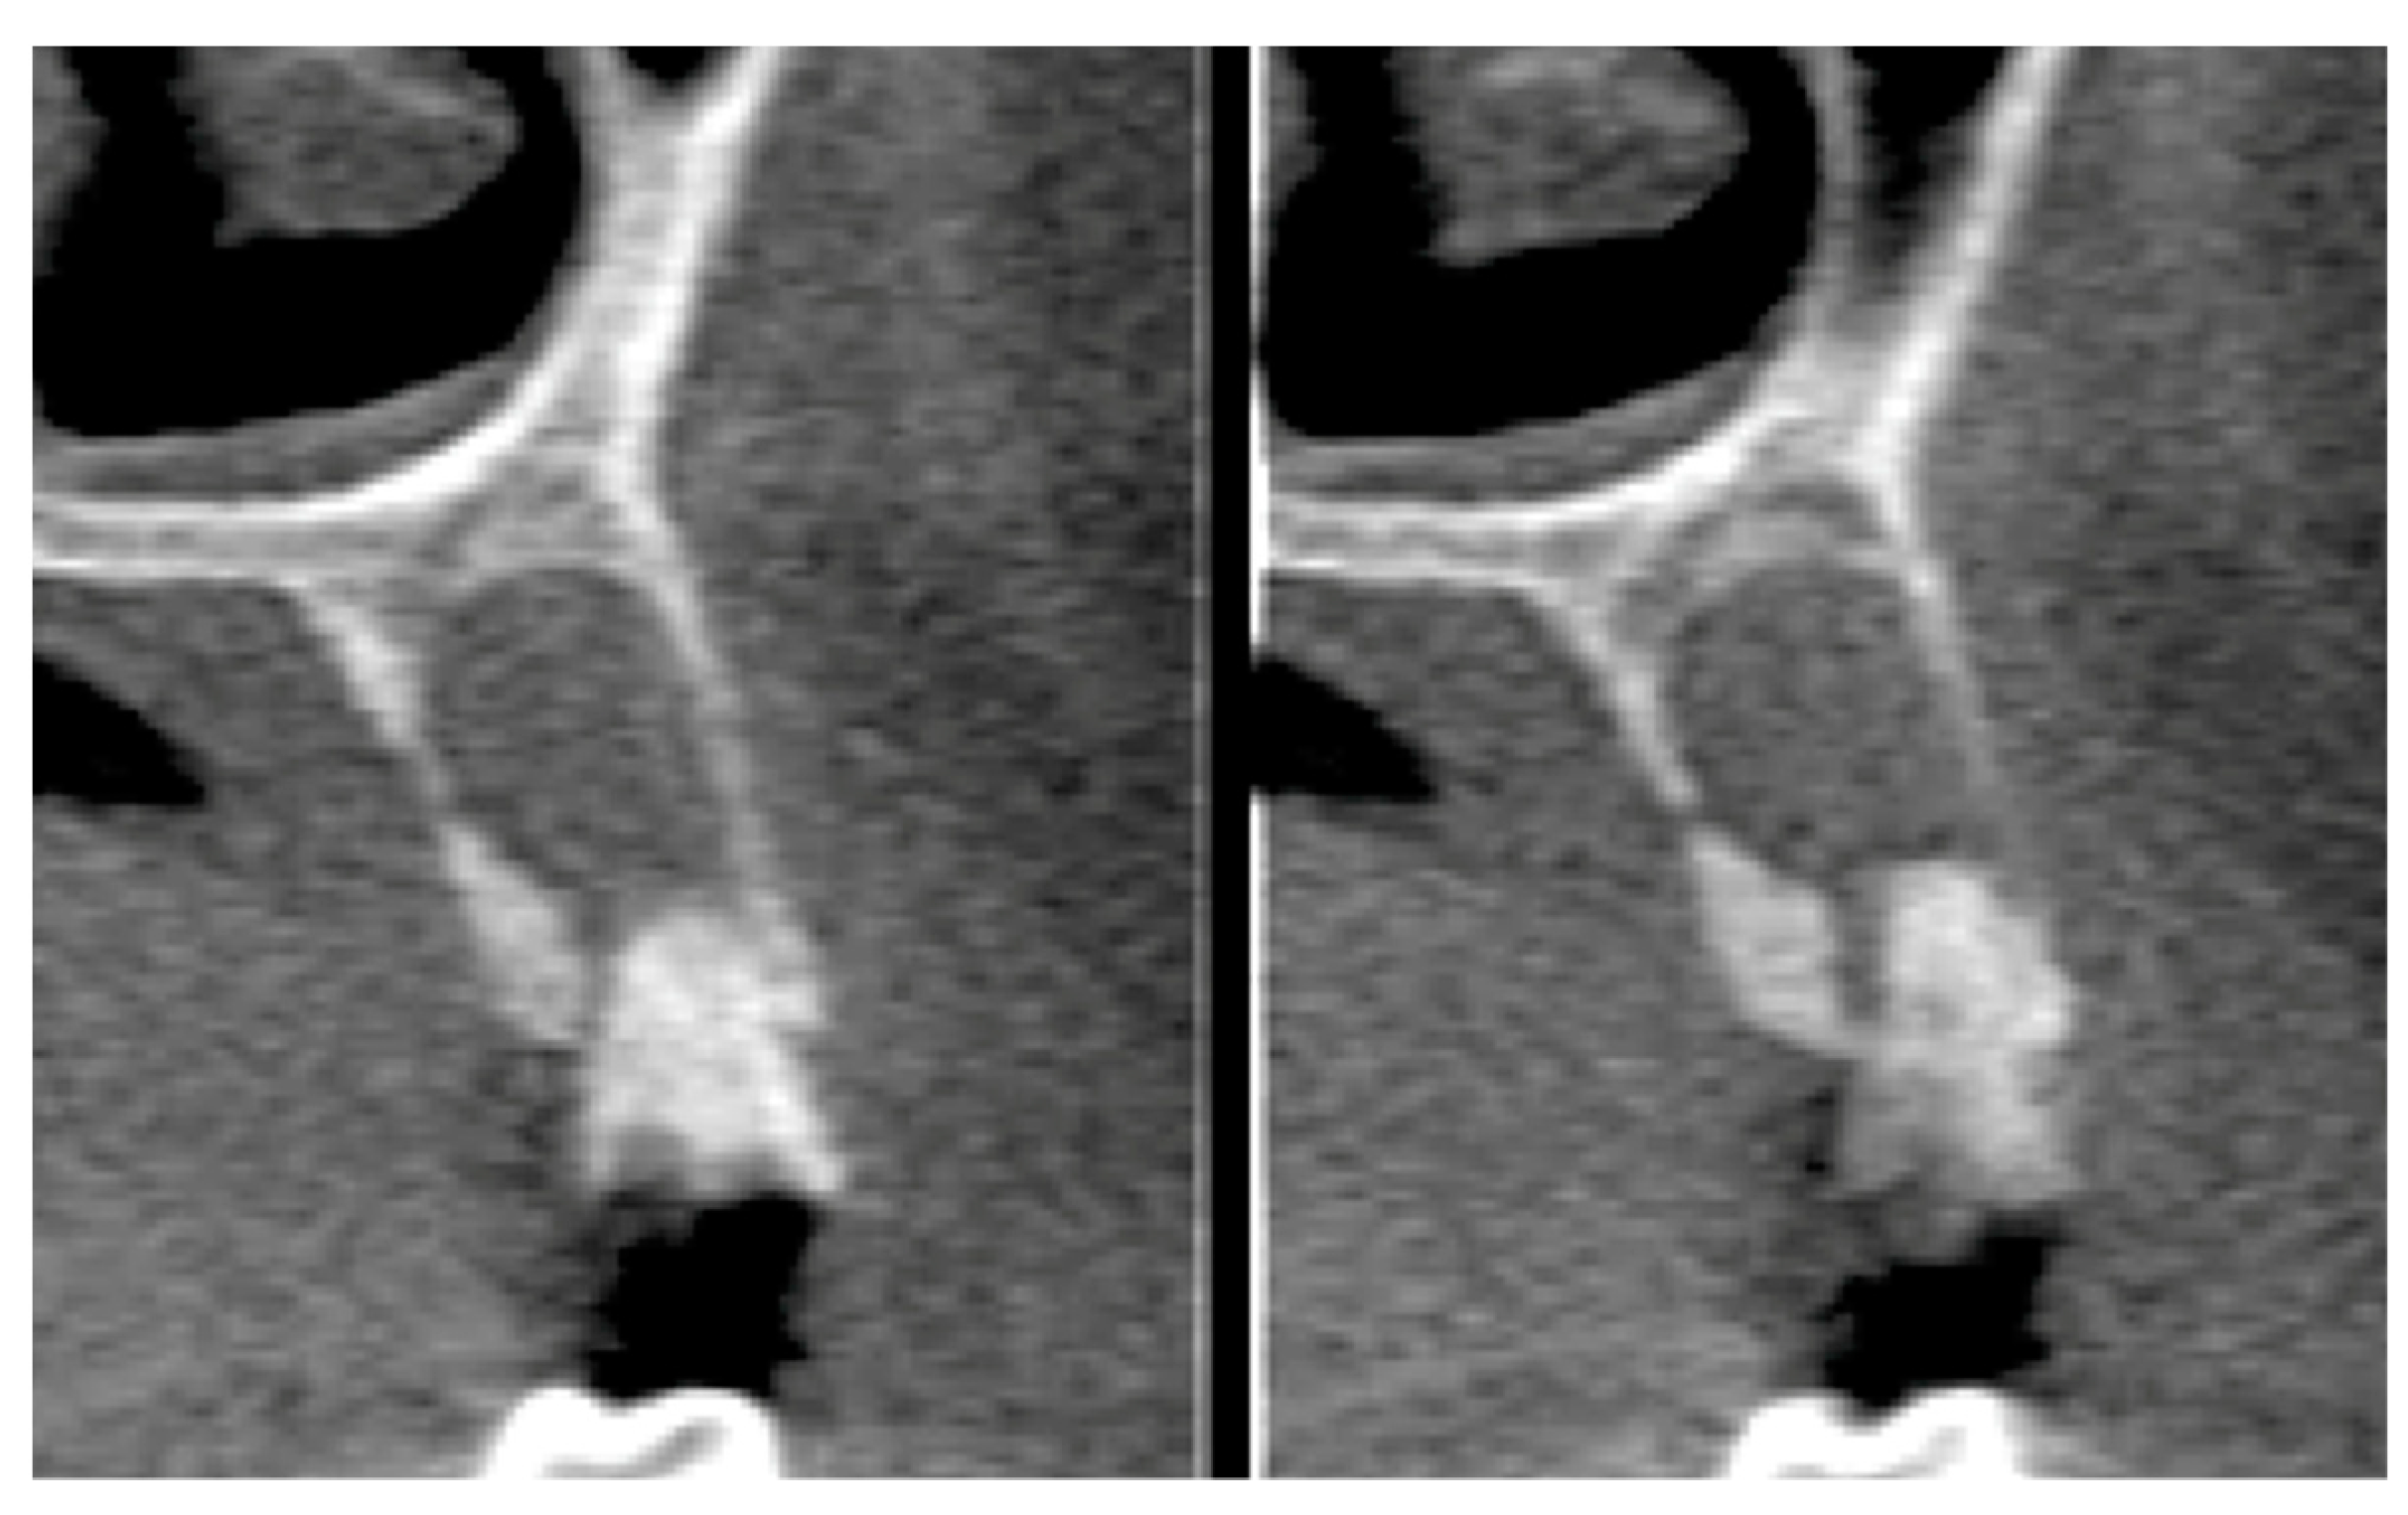

2.6. Tomographic Analysis